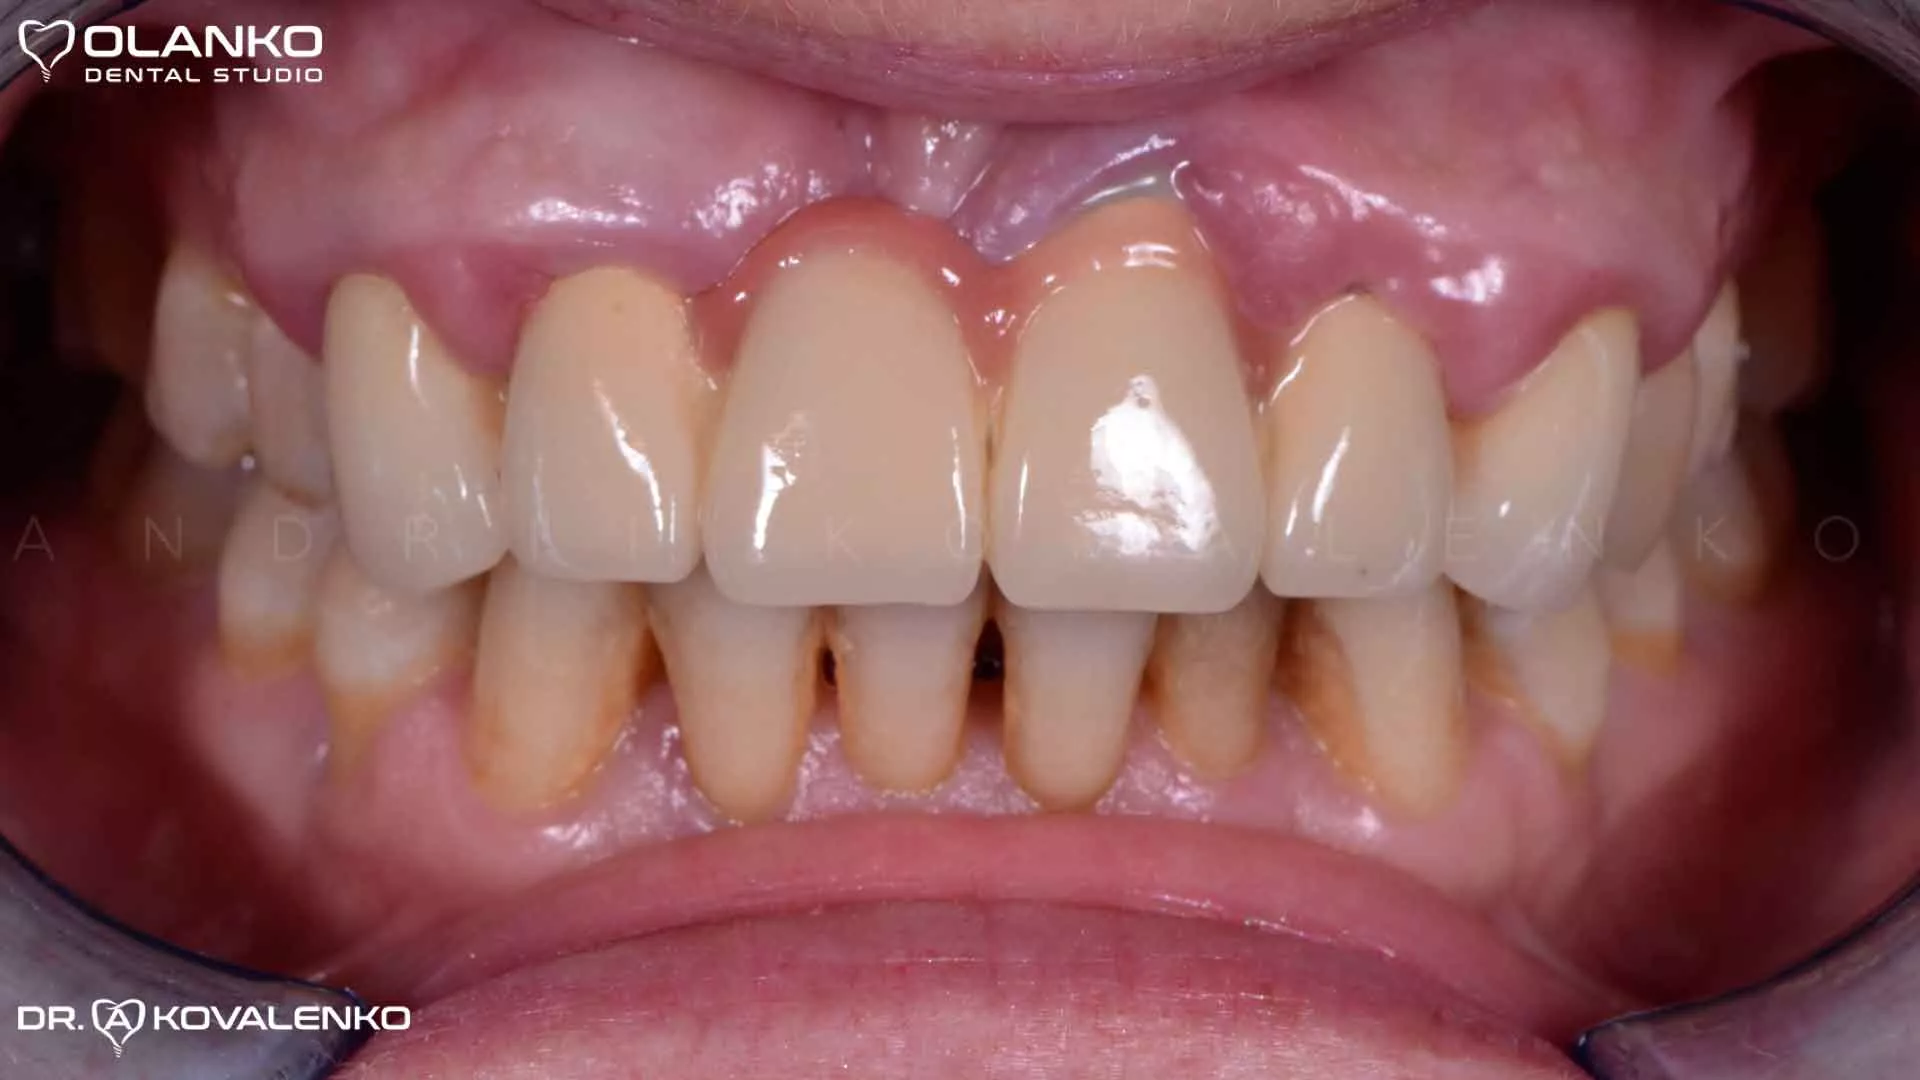

Пациентка обратилась с жалобами на болевые ощущения, подвижность и выделения гноя в области мостовидного металлокерамического протеза во фронтальном участке верхней челюсти

Фото ситуация до начала протезирования

Фото вид разрушенных зубов после снятия металлокерамического моста